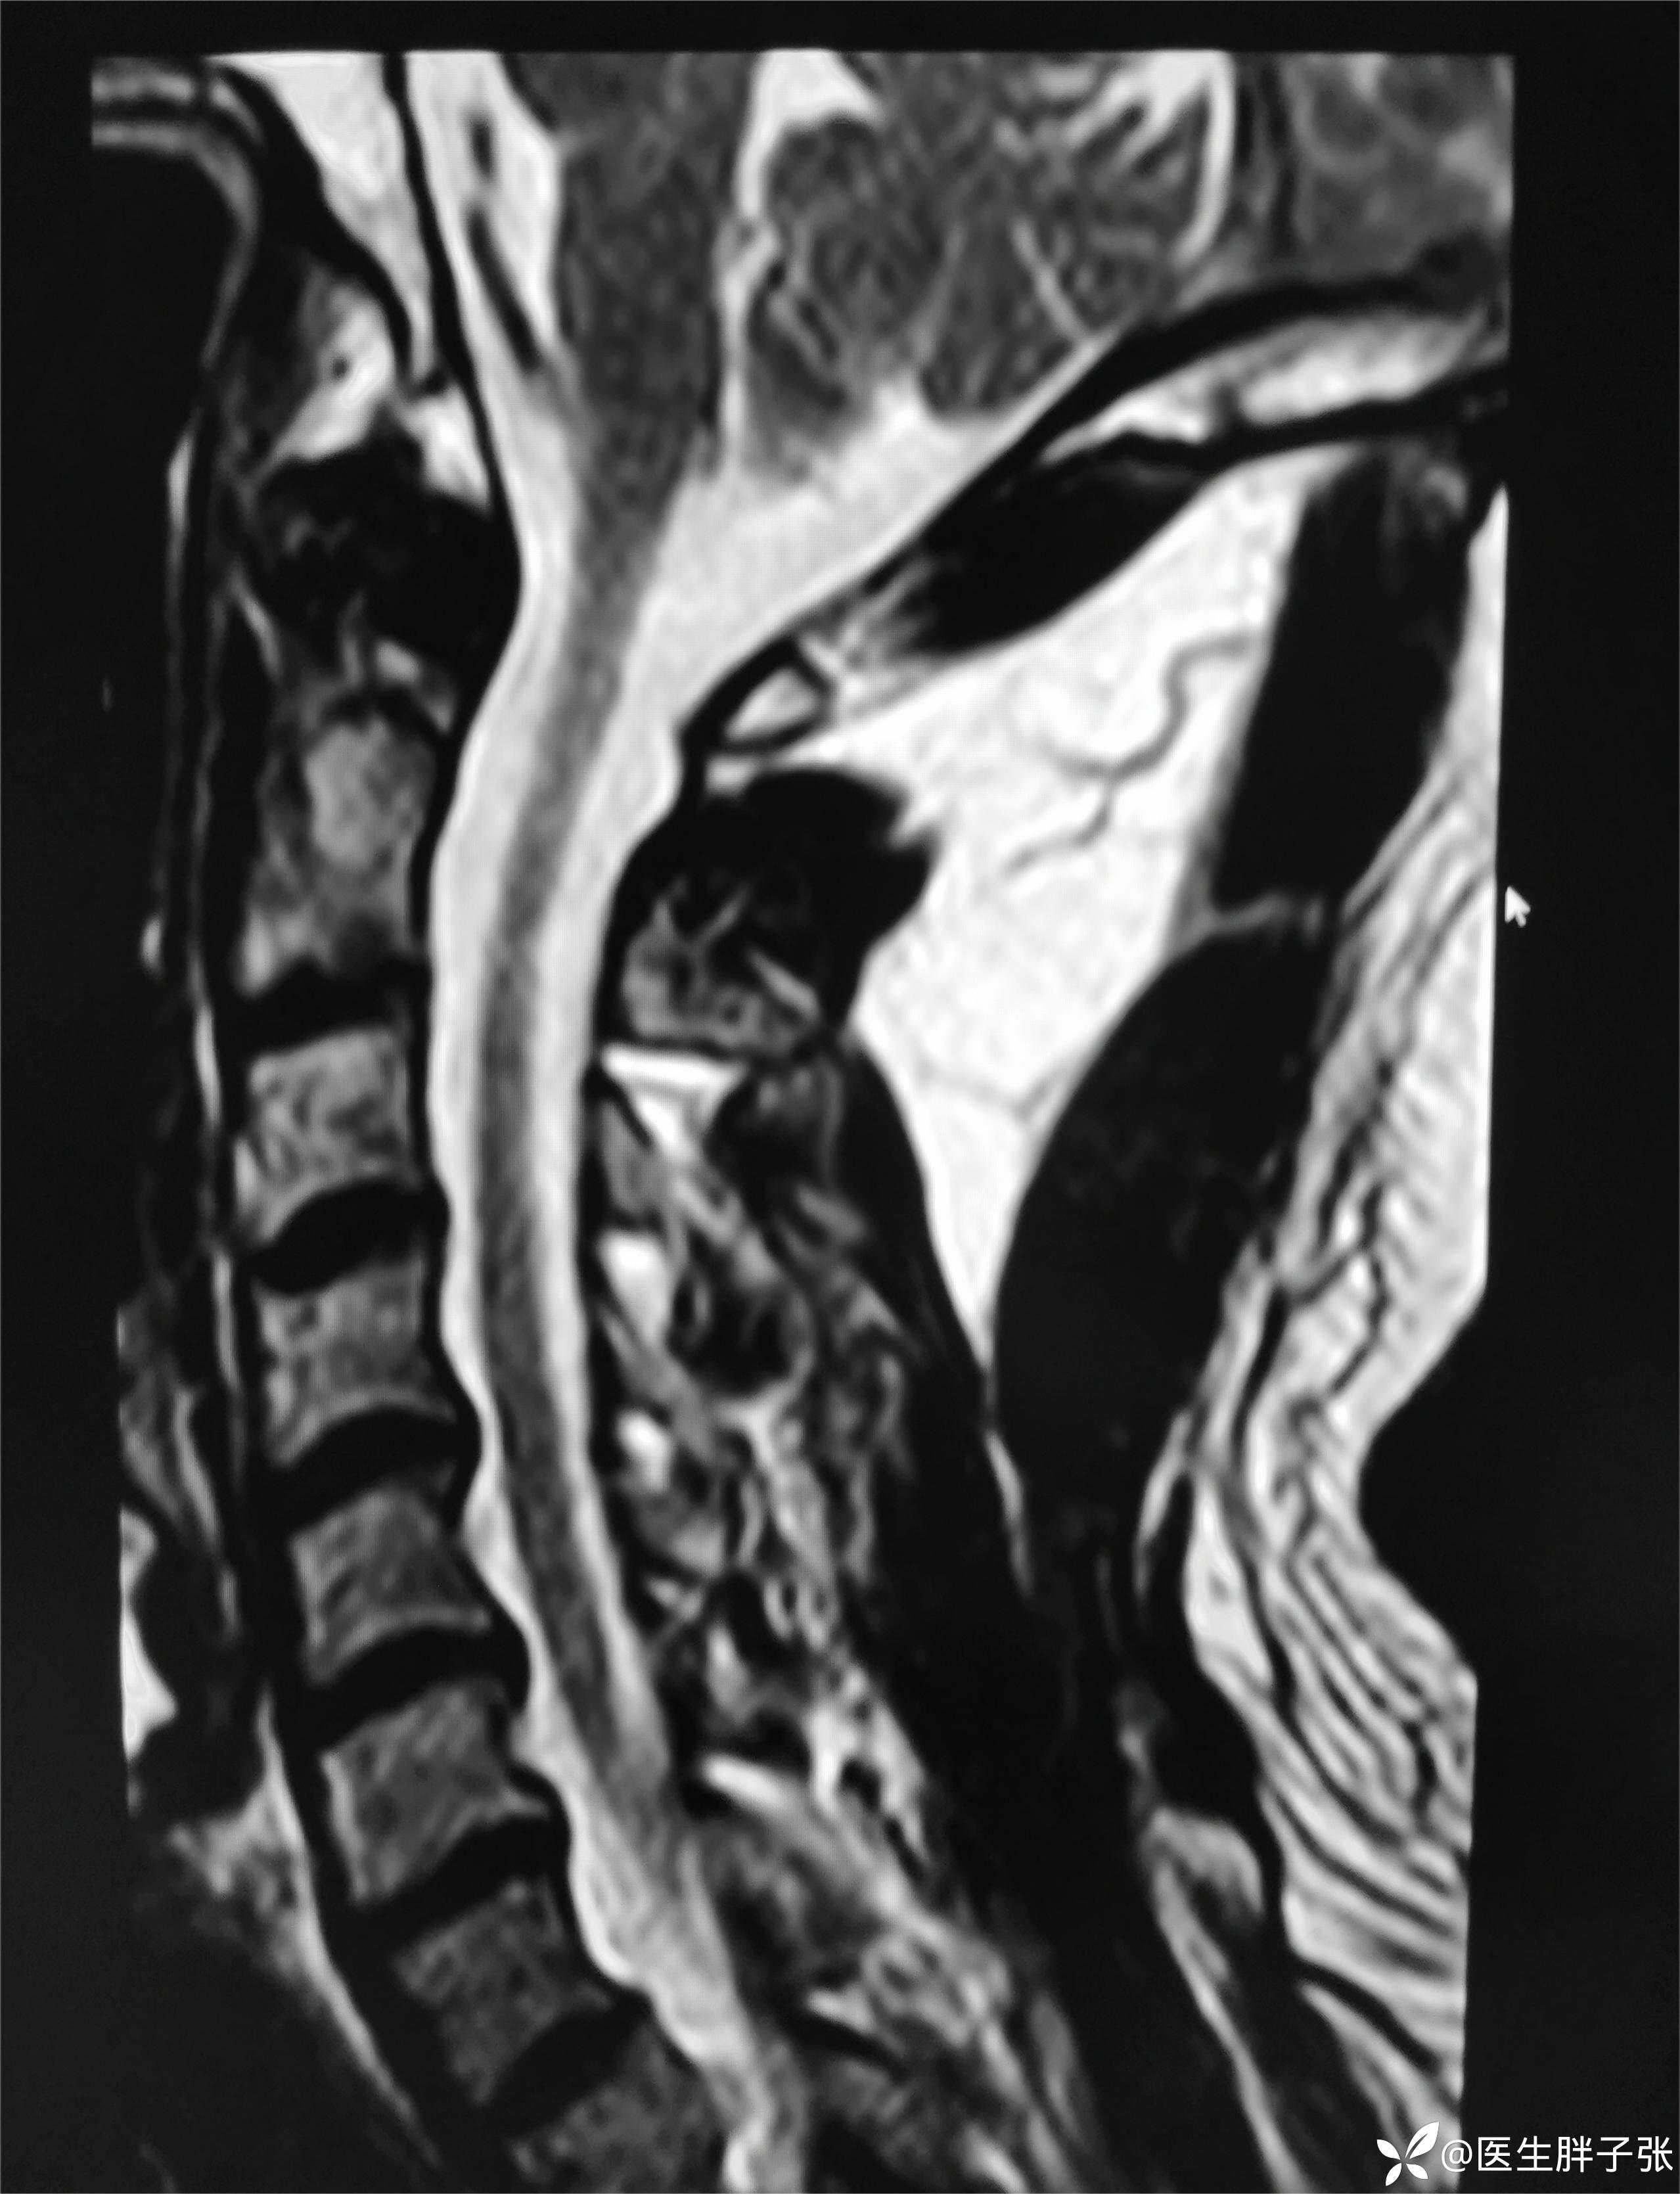

颈椎MR回报

头颈部CTA提示左侧椎动脉闭塞、右侧椎动脉开口中度狭窄、左侧颈内动脉动脉瘤。